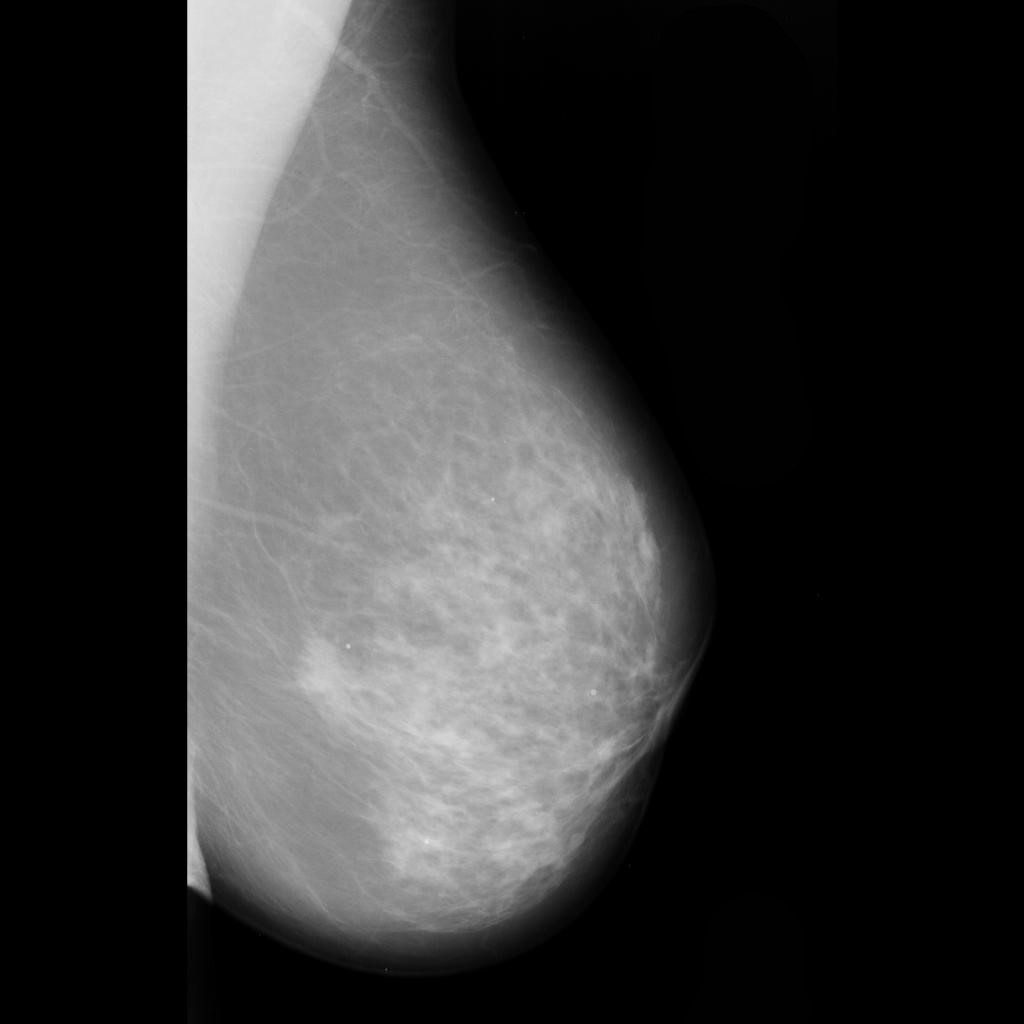

malignant